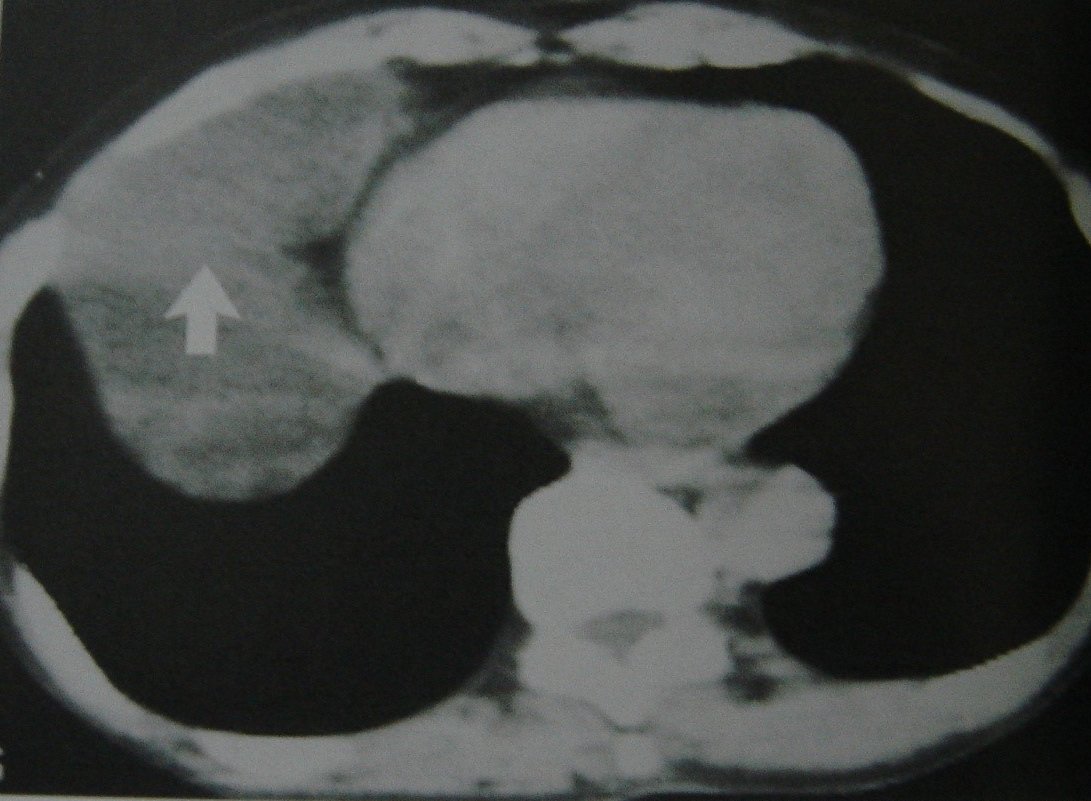

• Klinik, laborator və tomoqrafik üsullarla törəmənin təbiəti məlum olmursa rezektabelliyə görə qərar verilir (Şəkil 20). Rezektabel törəmələrdə kütlə əməliyyatla (torakoskopik və ya açıq) çıxarılır və histoloji müayinə edilir (həm diaqnostika, həm də müalicə məsələsi həll edilir). Qeyri-rezektabel törəmələrdə isə perkutan, bronxoskopik və ya torakoskopik yolla biopsiya edilir.

Şəkil 20. Divararalığında kütlə